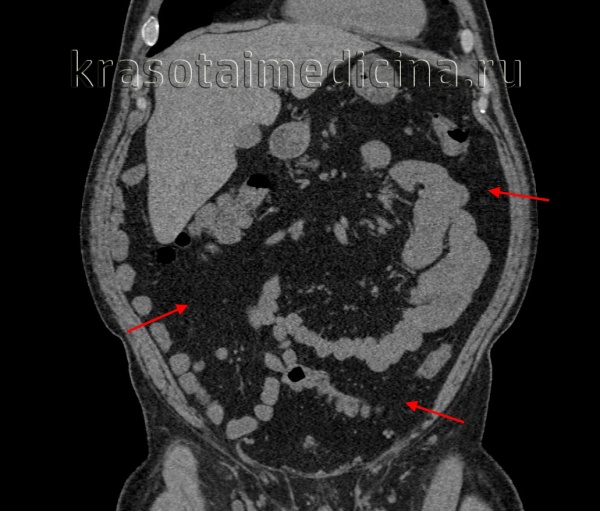

КТ ОБП. Избыточное количество висцеральной жировой клетчатки у пациента с повышенным индексом массы тела.